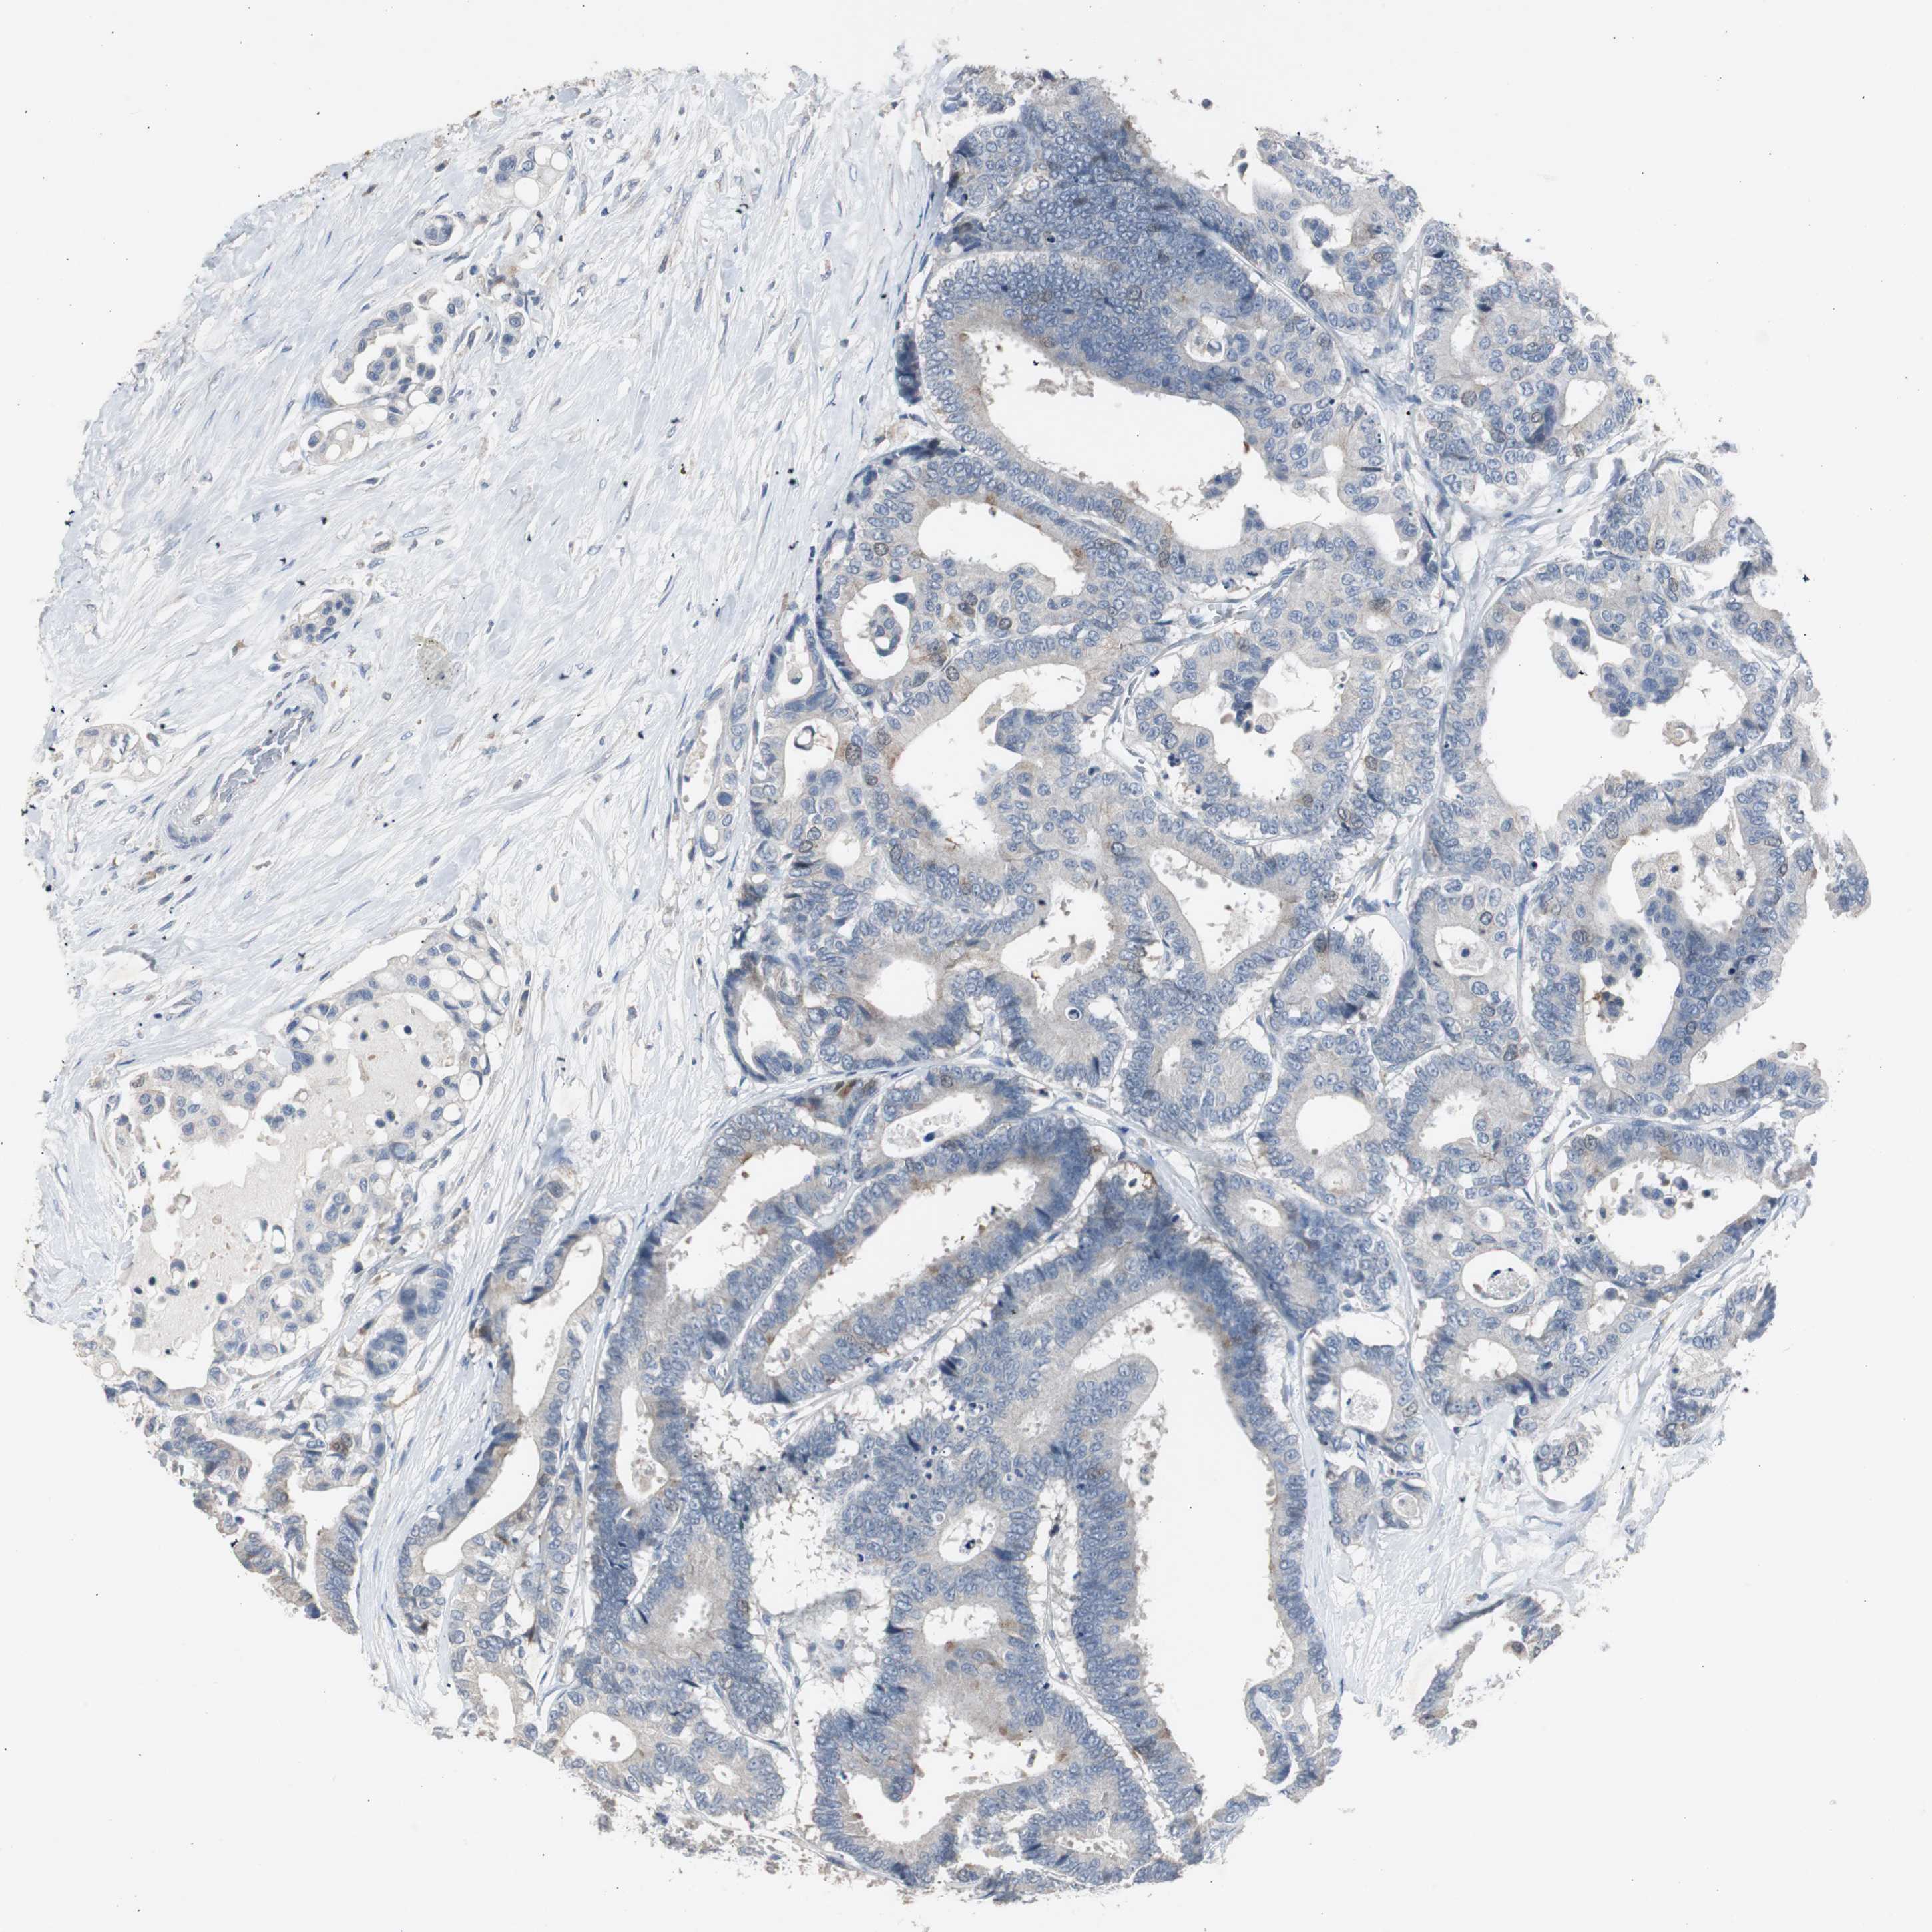

ANTIBODIES

AND

VALIDATION